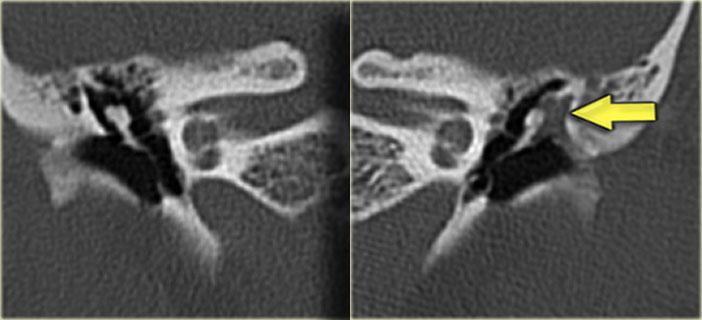

Hình ảnh bên trái của bệnh nhân nam 14 tuổi với điếc tiếp nhận hai bên.

Vôi hóa ống bán khuyên trên bên trái (mũi tên vàng).

Tai phải để so sánh (mũi tên xanh lam).

Hình ảnh mặt phẳng coronal của cùng bệnh nhân trên.